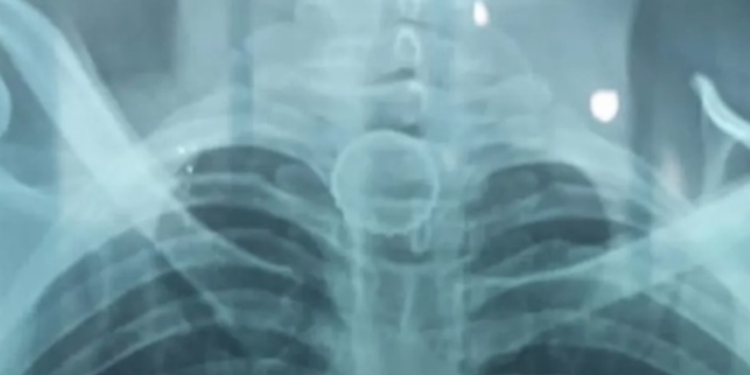

A tampa foi parar no esôfago e o homem começou a passar muito mal, indo parar no hospital. Ele precisou ser transferido para o Hospital do Juruá, em Cruzeiro do Sul, no Acre, onde foi confirmada a posição do objeto em exames de imagem.